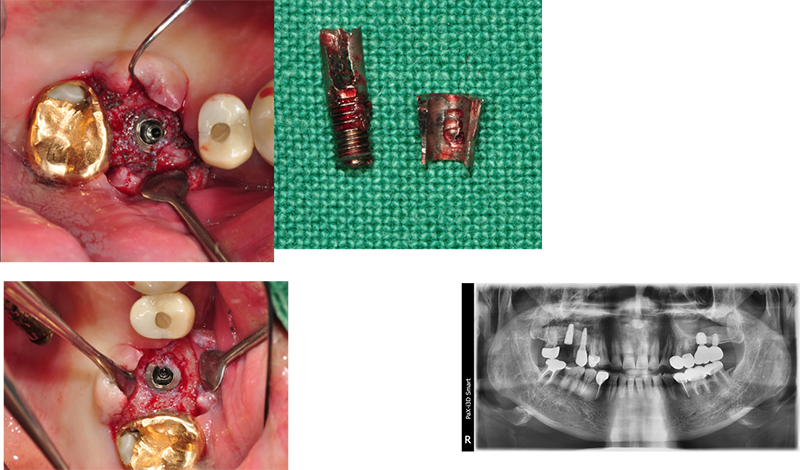

이 임상 케이스는 브릿지 타입을

싱글 타입으로 바꿔주기 위한 작업 중 일어난 작은 소동을 기록했다.

어벗을 풀다가 플렛폼에 있는

헥사가 망가졌다. 풀 수가 없었다. 4.4 mm 내경을 가진 solid ab 체결 드라이브를 이용하기로 했다.

먼저 Ezc 어벗의 직경을 다이아몬드 버로 살짝 다듬은 다음, 슬롯을 만들고, 이곳에 solid ab 드라이버가 삽입되도록 한다. 돌리면 쉽게 제거된다.

잇몸이 웃자랐다.

37번 abutment 파절, 뒤쪽에 8번이 보이고, fixture 직경이 5.0, 조금 흠집이 나도 된다는 생각으로 제거수술을

했다.

3번에

나눠서 겨우 제거한 경우